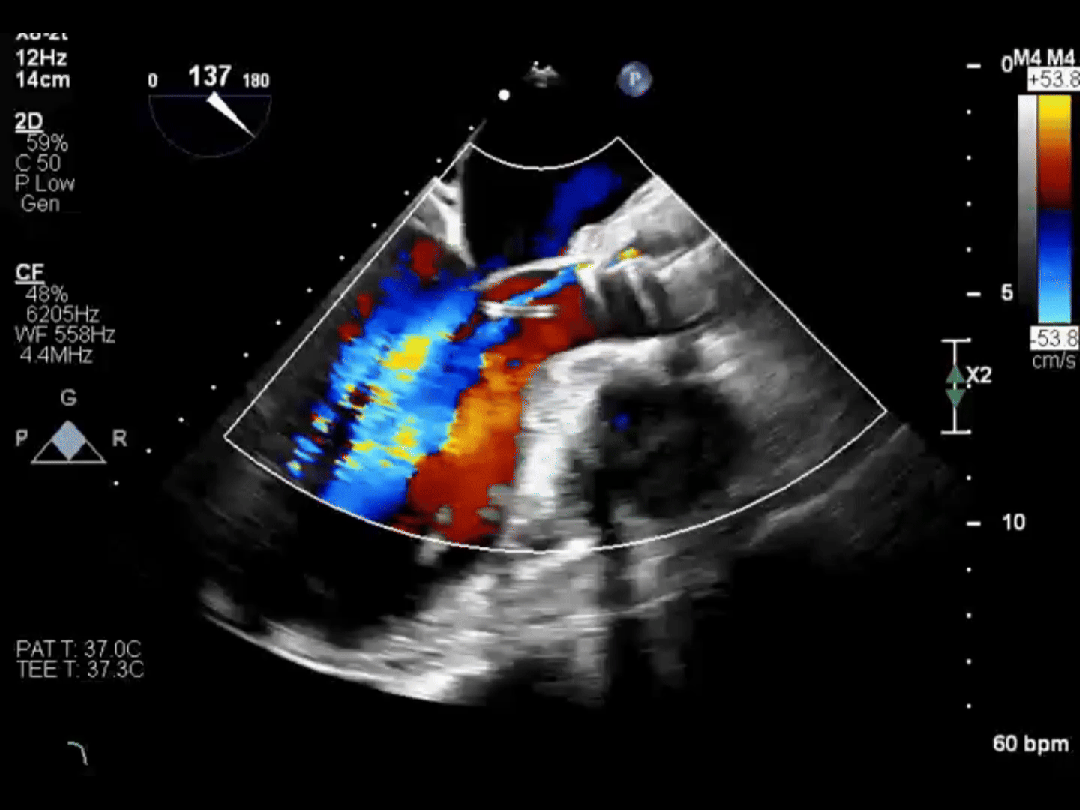

同样幸运的还有李爷爷。他因心脏二尖瓣脱垂导致血液严重反流,随时可能发生心衰。经过评估,医生为他选择了经导管二尖瓣钳夹术(TEER)。

手术中,医生通过大腿静脉送入特制夹子,在超声引导下精准夹合脱垂的瓣叶。整个手术不到 1 小时,李爷爷原本关不牢的「心门」变得「严严实实」,术后反流明显减少,充分彰显了团队的技术实力。